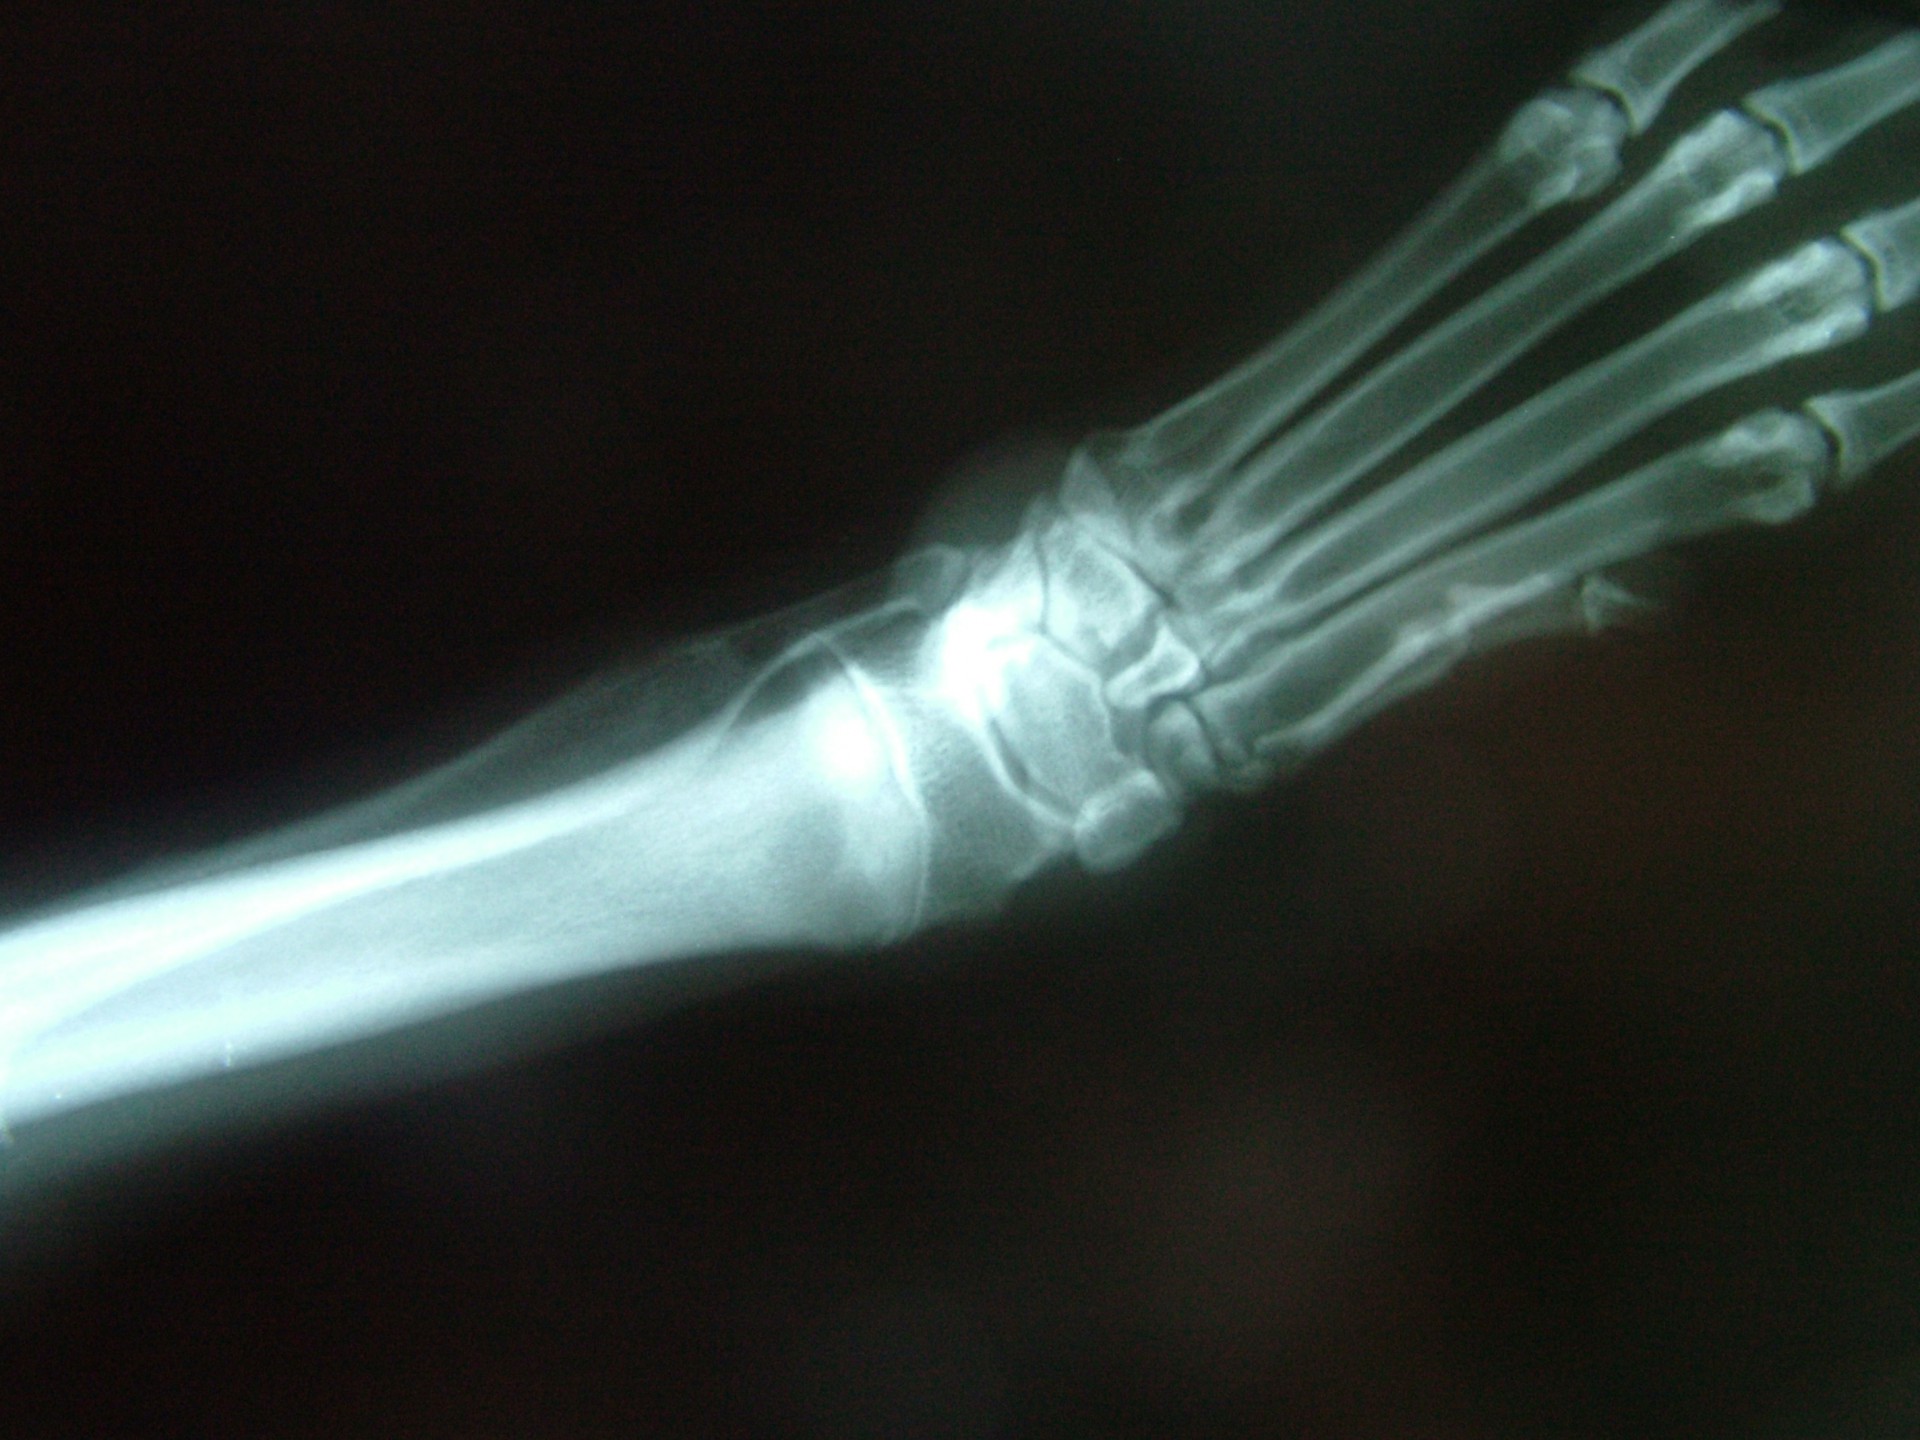

A könyökcsont növekedési zónájának záródása (short ulna)

A könyökcsont alsó epiphysisének lezáródása (short ulna) az alkar kifelé történő görbülését eredményezi (valgus állás). A klinikai tünetek (végtagdeformitás) mindig fokozatosan, lassan alakulnak ki, sok esetben a növekedési zóna lezáródásához vezető trauma nem igazolható. Az állat a lábát az elülső lábtőízület alatti területen kifelé fordítva tartja.A fizikális vizsgálat során fájdalom nem tapasztalható és az altatásban történő vizsgálat során a végtag deformitása nem szüntethető meg. A kiegészítő RTG vizsgálattal a könyökcsont alsó növekedési zónájának záródása egyértelműen igazolható. Ezek alapján a betegség az elülső lábtőízület lazaságától (carpal laxity) egyértelműen elkülöníthető. Mivel a végtagállási hiba már kölyök korban megjelenik fontos annak elkülönítése is, hogy örökletes úton (X-láb) vagy a növekedési zóna lezáródása következtében alakult ki a valgus állás.

Amennyiben a növekedési zóna lezáródása a végtag deformitásának oka és idejében felismertük a betegséget, a fékként szolgáló könyökcsont egy darabját eltávolítva (ulna osteotomia) az alkarcsont növekedése normalizálódhat. A lassú gyógyulás elengedhetetlen feltétele, hogy az állat még növendék korban legyen, így az alkarcsontnak is legyen lehetősége a növekedésre.Amennyiben a végtag növekedésére már nincs esélyünk, ill. a valgus állás genetikai vagy egyéb traumás eredetű, a műtéti korrekció során a görbült alkarcsontból egy ék kivágásával és az elvágott területek megfelelő irányba helyezését követően osteosynthesis-sel a végtag kiegyenesíthető.